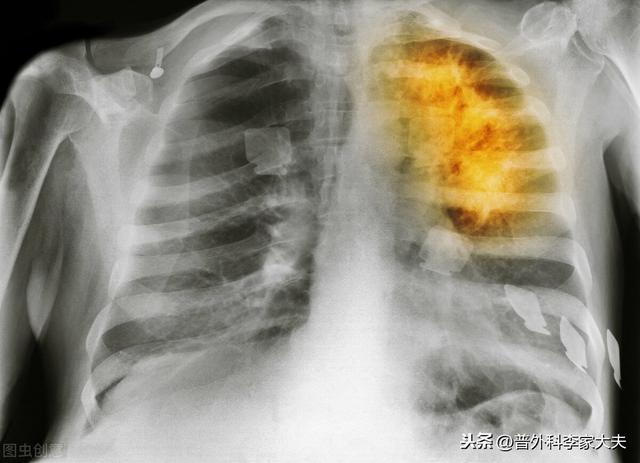

Il y a près de 800 000 nouveaux cas de cancer du poumon chaque année, et environ 85 % des patients sont atteints d'un cancer du poumon non à petites cellules, différent du cancer du poumon à petites cellules, qui est moins malin, et la plupart des patients aux stades I, II et IIIA peuvent être opérés, et la chirurgie est également la méthode de traitement la plus directe et la plus efficace. Le cancer du poumon à petites cellules peut également être opéré, mais seuls les cas très précoces et précoces peuvent l'être. Quelles sont les suggestions pour le cancer du poumon après l'opération ?

chirurgie pulmonaire par thoracoscopie

opération radicale du cancer du poumon